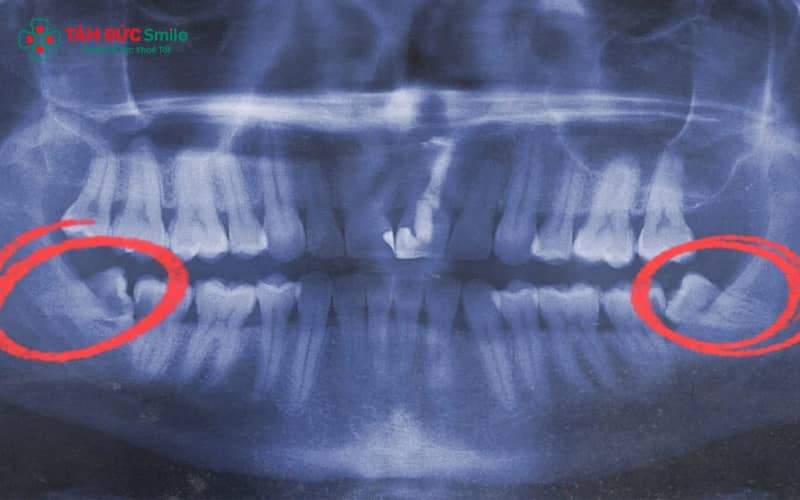

2.6 X-quang cho thấy răng khôn mọc lệch ra má hoặc đâm vào răng số 7

Phương pháp chẩn đoán chính xác nhất là chụp X-quang răng khôn. Hình ảnh X-quang giúp bác sĩ phát hiện răng khôn mọc lệch ngang, mọc ngầm hoặc đâm vào má, răng số 7, từ đó đưa ra phương án điều trị phù hợp, thường là nhổ răng khôn an toàn để ngăn biến chứng.

3.1 Thăm khám và chụp X-quang để đánh giá vị trí răng khôn mọc lệch

- Chụp X-quang răng khôn (phim toàn cảnh hoặc Cone Beam CT 3D) giúp bác sĩ xác định chính xác vị trí mọc, hướng mọc (lệch ngang, mọc ngầm, đâm vào răng số 7) và mức độ ảnh hưởng đến xương hàm.

- Dựa trên hình ảnh X-quang, bác sĩ sẽ đưa ra phác đồ điều trị: theo dõi, điều trị tạm thời hay tiến hành nhổ răng khôn.

- Đây là bước quan trọng giúp hạn chế rủi ro khi nhổ và tránh các biến chứng như tổn thương dây thần kinh, xoang hàm.